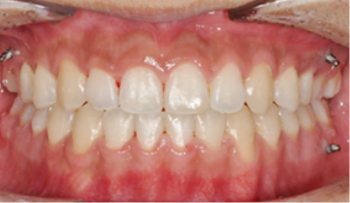

​​​​​​​Case 01. 덧니 & 치열 불규칙

덧니가 있거나 치열이 불규칙한 경우, 심미적으로도 보기에 좋지 않지만, 기능적으로도 본연의 역할을 상실하게 됩니다.

이 경우 교정 치료 방법은 크게 치아를 빼고 하는 방법과 치아를 빼지 않고 교정하는 방법으로 나뉩니다.

교정 치료 Before & After

• 덧니 & 치열 불규칙 교정 치료 후

After